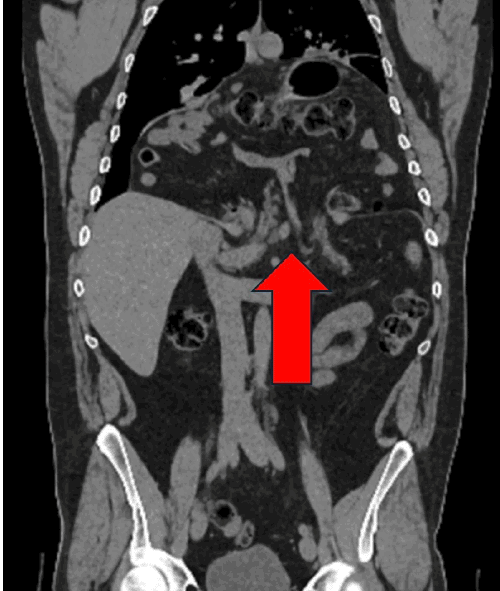

The patient subsequently underwent a laparoscopic paraesophageal hernia repair. Intraoperatively, the hiatal defect was noted to be significantly enlarged. Reduction of the herniated viscera commenced with careful mobilization and retrieval of the small bowel from the mediastinum (Figure 2). The greater omentum and transverse colon also required extensive mediastinal dissection before complete reduction into the abdominal cavity could be achieved. The stomach was found to be densely tethered within the mediastinum, necessitating division of the short gastric vessels to facilitate its full reduction. Following extensive blunt and electrocautery dissection, the stomach was successfully repositioned intra-abdominally, and both diaphragmatic crura were clearly visualized (Figure 3).

Figure 2. Intraoperative Laparoscopic Reduction of Herniated Viscera. Published with Permission

This image captures a moment during the meticulous reduction of herniated contents, showing loops of bowel and portions of solid organs being carefully mobilized and returned from the mediastinum through the large diaphragmatic defect into the abdominal cavity